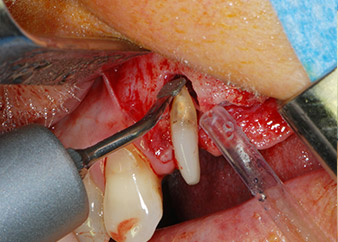

Then the apex was abraded with the same instrument to remove residual infected apical tissue and to reduce possible accessory root-canal ramifications (apicoectomy) (Fig. 5). A retrograde filling was not necessary because the orthograde filling had just been revised.

Prior to implant placement, infected tissue was removed from the alveolar bone in the implant site and around the abutment teeth with an insert originally designed for bone shaping and collecting bone chips (Piezomed, insert B5) (Figs. 6 and 7).